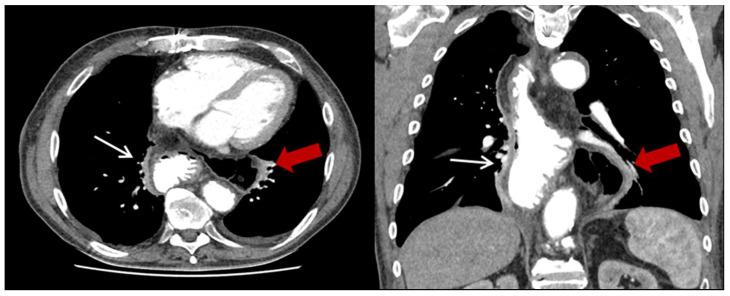

A retrospective single-center analysis was performed on patients who underwent Ivor Lewis esophagectomy between January 2009 and April 2018. Computed tomography scans and patient files were reviewed to identify the PHH.

方法

对2009年1月至2018年4月期间接受艾弗·刘易斯食管切除术的患者进行回顾性单中心分析。回顾计算机断层扫描和患者档案以确定PHH。

纳入306例患者(152例行HMIE;154例行OE)。其中,23例患者(8%)发生PHH。大多数患者(13/23,57%)在诊断时无症状,仅有4例患者(17%)因嵌顿而急诊就诊。与OE相比,HMIE后PHH的发生率显著更高(13.8%对1.3%,<0.001)。在单因素或多因素分析中未发现其他PHH发生的危险因素。19/23例患者(83%)接受了PHH的手术修复。手术修复后PHH的复发率为32%(6/19例患者)。